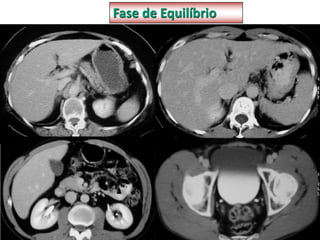

MEIO DE CONTRASTE

Fase Arterial

Fase Portal

Fase de Equilíbrio